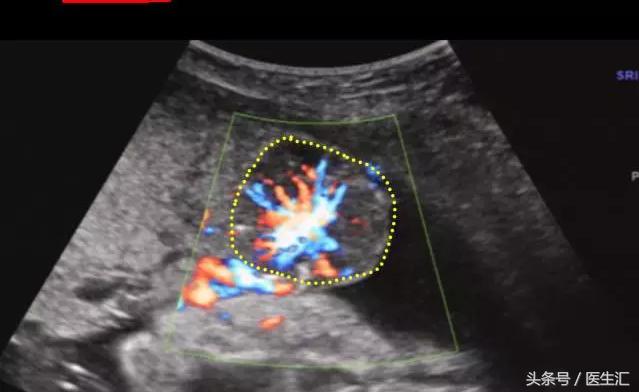

4.胎盘血管瘤:位于胎盘实质内或突向羊膜腔,回声较均匀,边界清。(见图5黄色圈内)

图5,胎盘位于子宫前壁,厚47mm,成熟度Ⅰ度,胎盘局限,胎盘内见一低回声区大小约40mm×35mm,边界清,内见丰富血流信号。